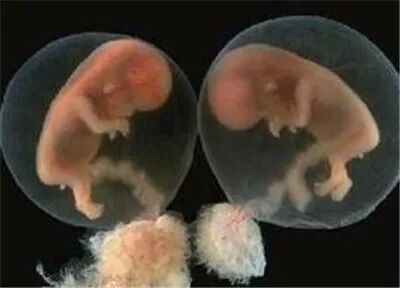

原来依萍怀的是葡萄胎,医生检查后发现,怀孕三个来月的肚子应该还不会隆起,可依萍的肚子却像怀孕五个月那么大,而据医生介绍,葡萄胎就是妊娠后胎盘绒毛滋养细胞增生,间质高度水肿,形成大小不一的水泡,水泡间相连成串,形状就像葡萄一样。葡萄胎的病人的子宫会明显大于停经的月份。

很快,依萍在医院接受了刮宫手术,手术顺利,出血不多。刮出组织内完全是一串串的小水泡,是非常典型的葡萄胎。但徐医师强调,“葡萄胎病人不是刮宫完就治疗结束了,术后需要定期监测血HCG指标,观察是否下降理想;此外,还需要B超复查,如出现宫内组织残留,还需要再次清宫;葡萄胎病人约有半数左右病人可能需要再次清宫。”